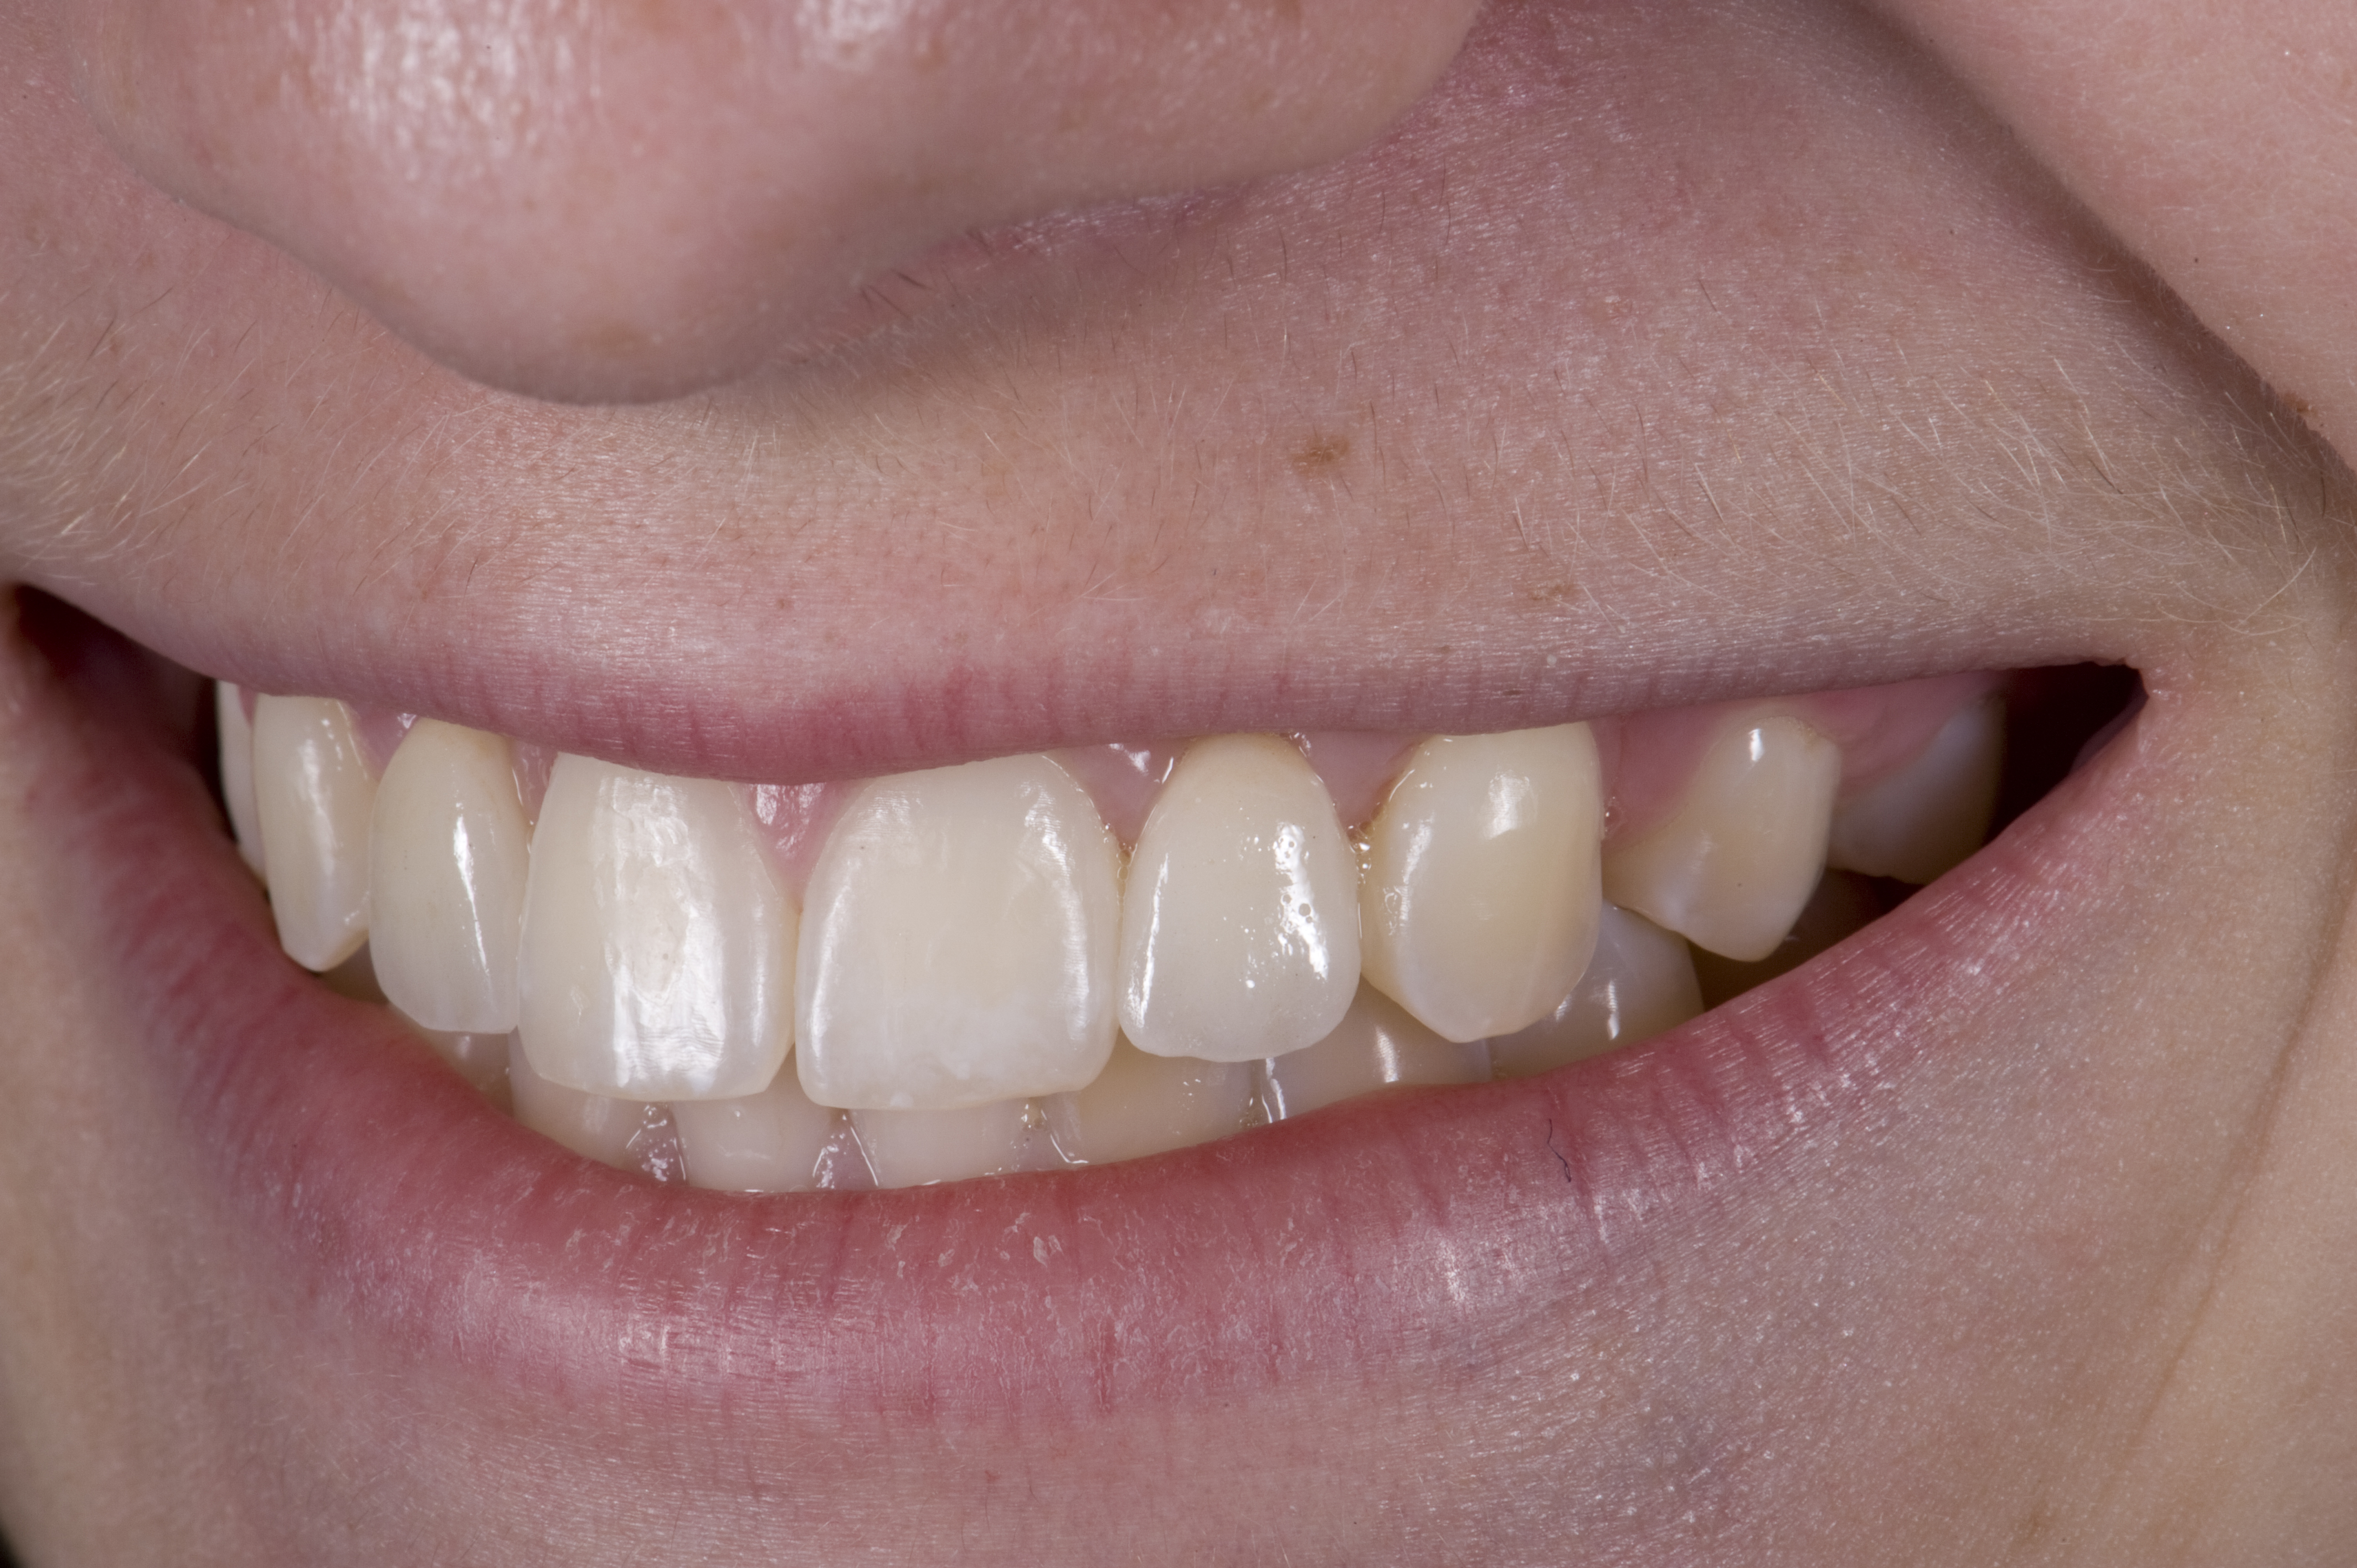

When the patient returned, the fit was evaluated in the mouth. Once verified, the internal surface of the framework was etched with a 9.5% hydrofluoric acid for 90 seconds and then salinized. After etching the enamel surface with phosphoric acid for 30 seconds and applying the primer (Single Bond Plus, 3M ESPE) to both the internal surface of the framework and the enamel, the zirconia bridge was bonded with a dual-cure resin cement (RelyX™ ARC, 3M ESPE). After the procedure, the patient ended up with a long-term, high-strength esthetic restoration advantaged by the bonding potential of fledspathic ceramic (Figure 20 through Figure 24). Six years after placement, the prosthesis had remained in place with no complications.

(20.) Facial view of final single-wing, modified zirconia resin-bonded bridges.

Figure 20

(21.) Smile view.

Figure 21